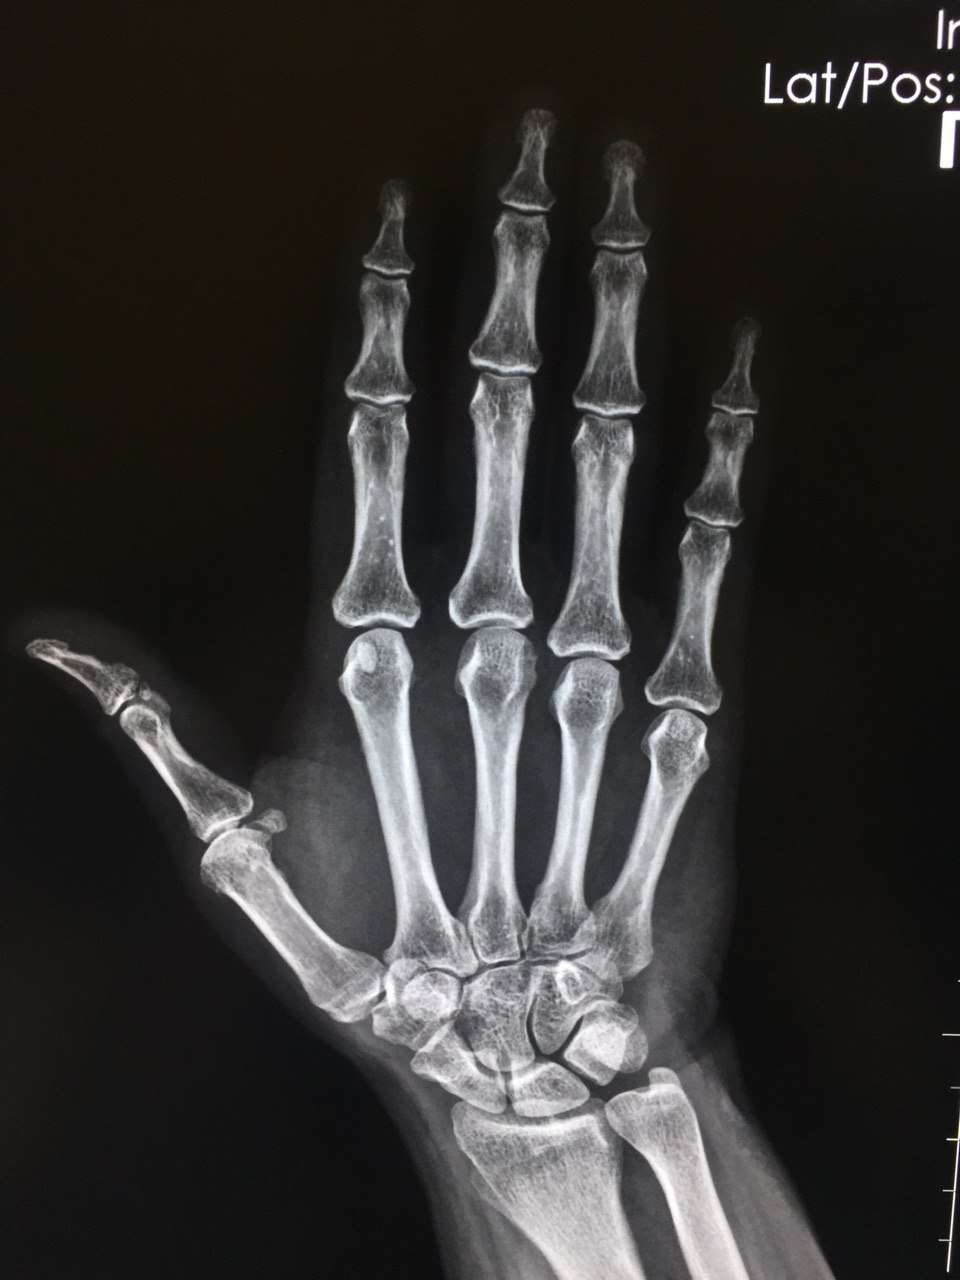

Коллеги,добрый вечер! Если не затруднит, ваше мнение по поводу конгруэнтности костей запястья. Боли в области 1пальца, направляющий д-з «щелкающий палец»

Аunt Jemima

Взаимоотношение в суставах не нарушено